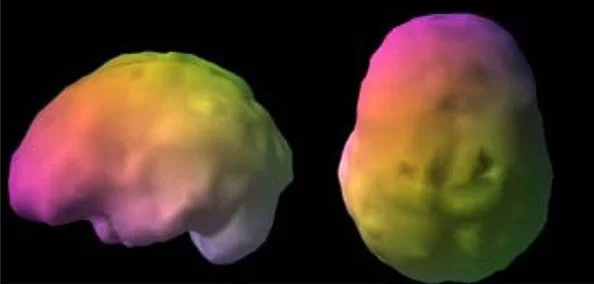

Cintilografia Cerebral com Trodat e Cintilografia de Perfusão Cerebral:

- Cintilografia Cerebral com Trodat: Avalia a função cerebral e pode ajudar a diagnosticar doenças neurológicas como a doença de Parkinson.

- Cintilografia de Perfusão Cerebral: Mede o fluxo sanguíneo no cérebro e é crucial para identificar áreas de diminuição do fluxo associadas a doenças neurológicas.